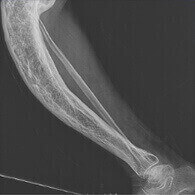

Kemik deformitesi

İki yıl boyunca dirseğim çok acıdı, uzmana ulaşmam için zamanım yoktu. Bir şekilde merhemlerle ara verdim, daha kolaylaşıyor gibiydi ve sonra dirsekte bursitte olduğu gibi aniden bir yumru belirdi. İnanılmaz derecede korktum! Karım sayesinde eklemlere iyi bakmam için ısrar etti, Aspercreme 'İ getirdi. Birkaç hafta içinde şişlik azaldı, ağrı tamamen durdu. Sonunda eskisi kadar sağlıklı hissediyorum!